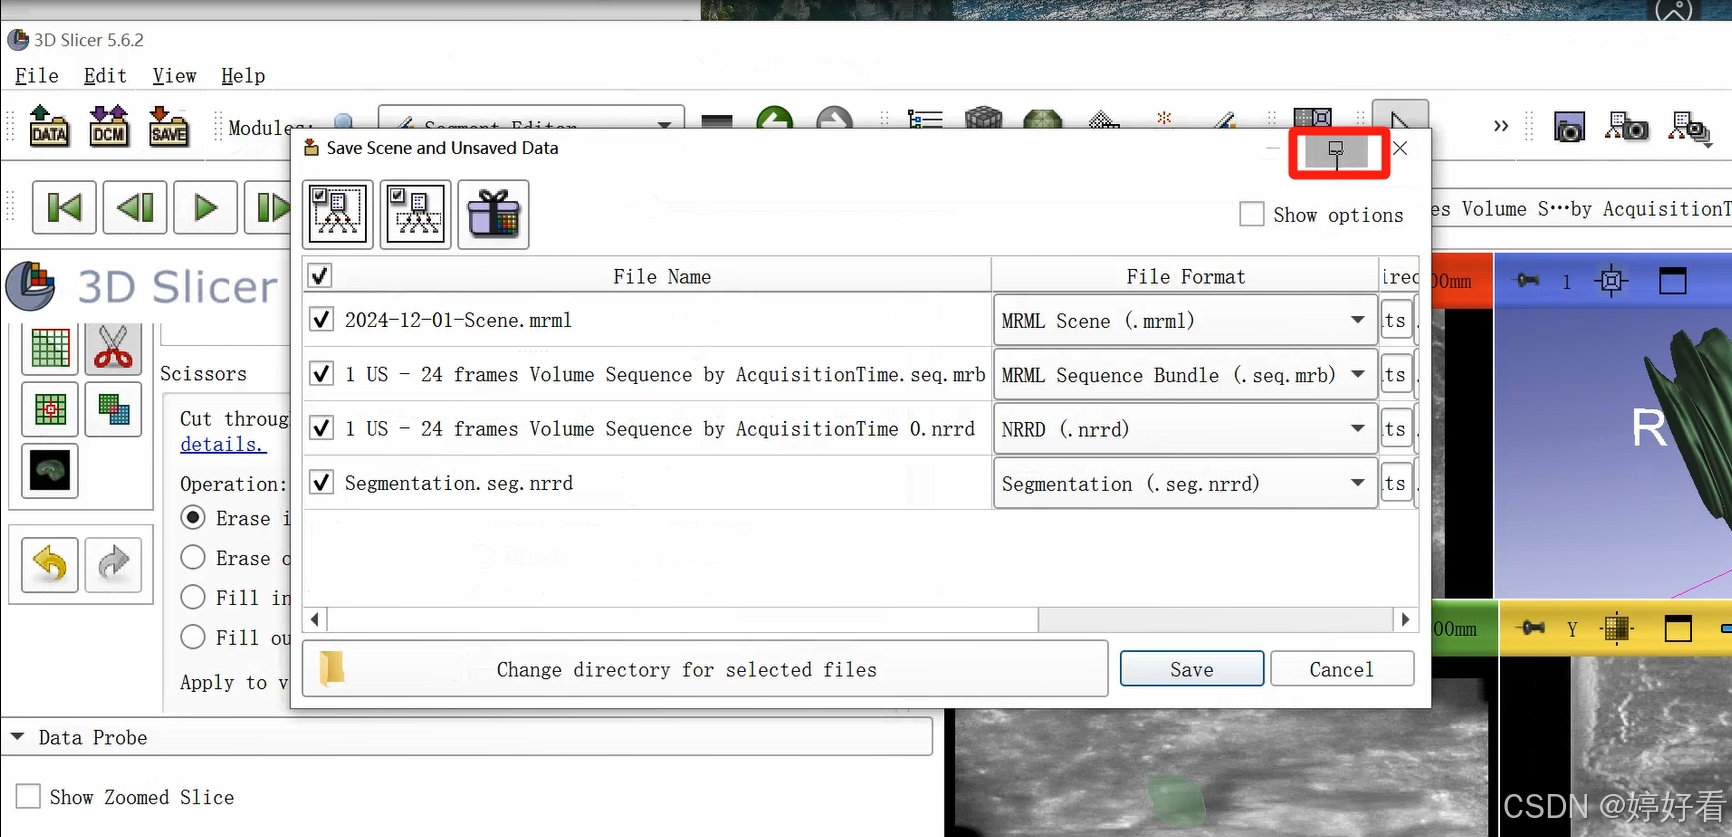

将对话框放大,可以修改单个文件的保存路径。